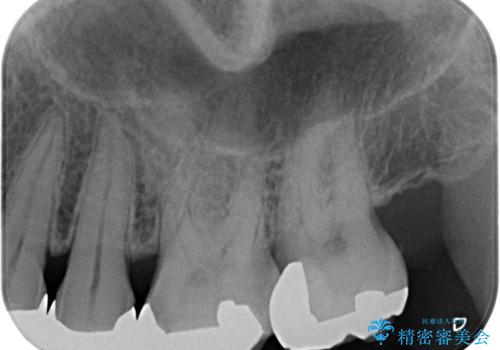

奥歯の虫歯 ゴールドインレーでの修復処置

- メンテナンスで3年ぶりにいらっしゃた患者様です。

検査の結果虫歯が確認されたため、治療を進めることとなりました。

- 左上7 ゴールドインレー 77,000円費用は治療当時の料金となります